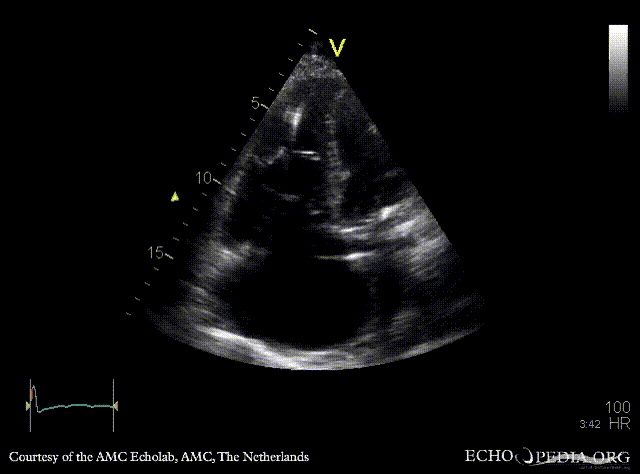

| Severe tricuspid regurgitation

| A4CH: dilated right ventricle and right atrium, pacemaker lead in situ